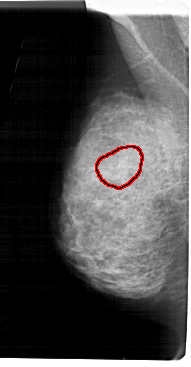

A_1939_1.RIGHT_MLO

LEFT_MLO LINES 5491 PIXELS_PER_LINE 2851 BITS_PER_PIXEL 12 RESOLUTION 43.5 OVERLAY

FILE: A_1939_1.LEFT_CC.OVERLAY

TOTAL_ABNORMALITIES 1

ABNORMALITY 1

LESION_TYPE CALCIFICATION TYPE AMORPHOUS DISTRIBUTION SEGMENTAL

ASSESSMENT 4

SUBTLETY 3

PATHOLOGY BENIGN

TOTAL_OUTLINES 1

BOUNDARY